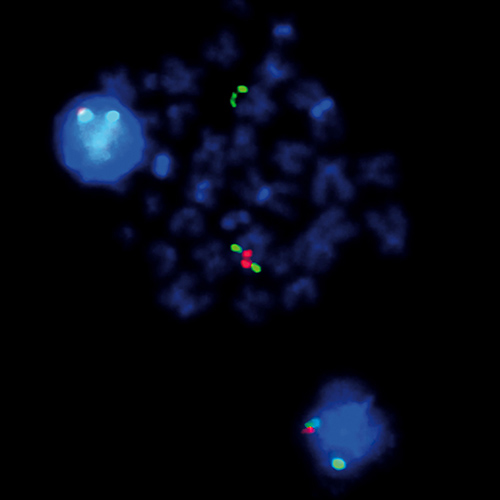

IVD ALK (2p23) Break - XL for BOND product photo

IVD ALK (2p23) Break - XL for BOND

or REQUEST a bulk quote.